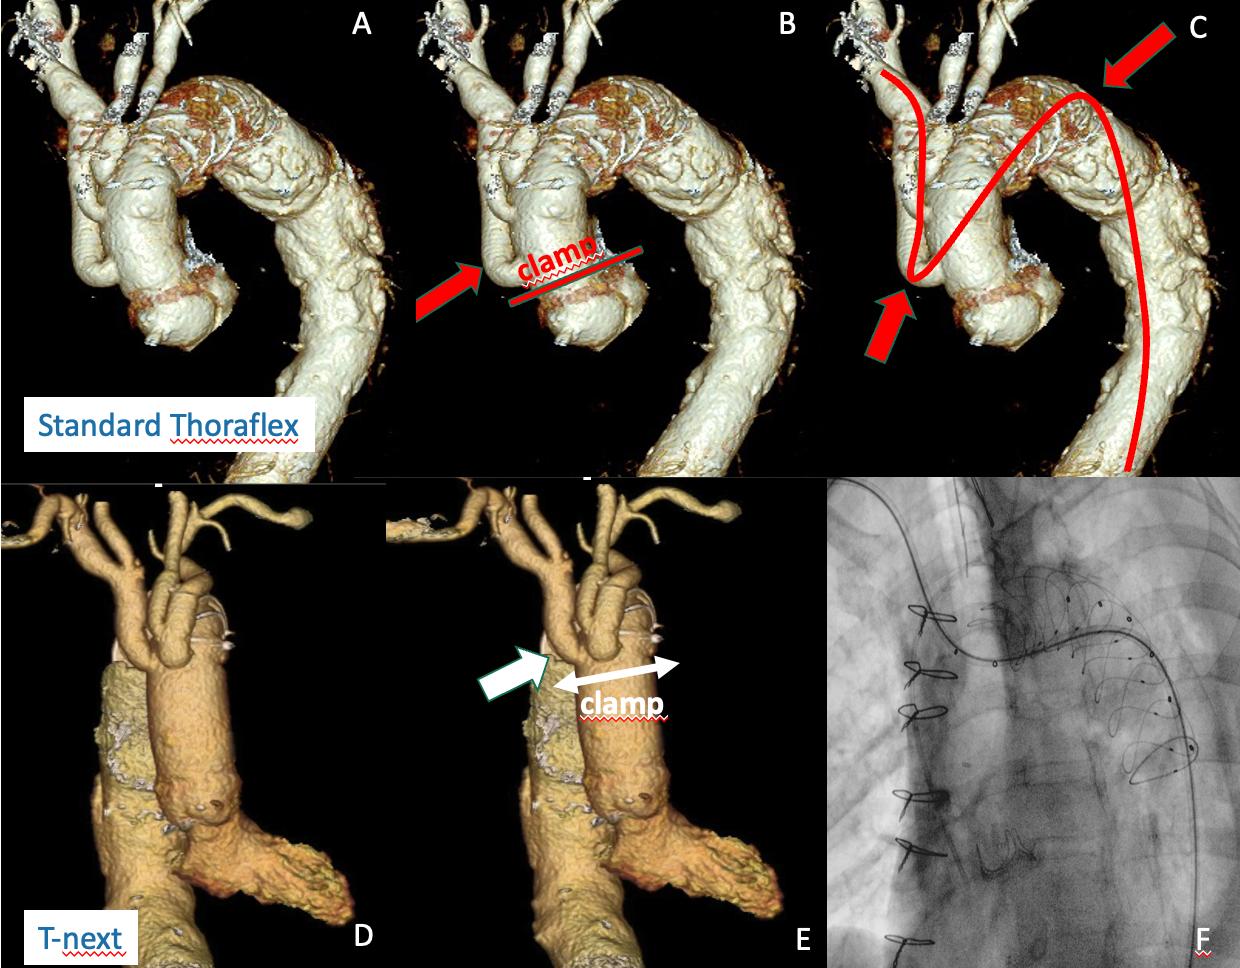

Aortic pathology is progressive in its nature and aortic reinterventions, proximal on the aortic root and distal on thoracoabdominal aorta, are often required following a Frozen Elephant Trunk (FET) operation.

Most of the currently available FET grafts were designed to recreate normal aortic arch anatomy with the distal anastomosis performed distal to the left subclavian artery. However, most aortic surgeons now perform the distal anastomosis more proximally (zone 0, 1 and 2). With the consequential proximalisation of the side branches, access to the aortic root becomes hampered as it requires a very low aortic clamp. Moreover, endovascular thoracoabdominal aorta repairs could also be more difficult as the visceral vessels are arduously cannulated from an upper body access with the double angulation that current FET grafts generate (see Fig. 1 A, B, C below).

T-next is a modified Thoraflex graft with a new distal and transverse arrangement of the side branches that has been designed to simplify proximal root and distal endovascular thoracoabdominal secondary interventions (Fig 2) (1).

A) Currently available FET grafts fail to facilitate secondary proximal and distal interventions if distal anastomoses are being performed in zones 0, 1 and 2; B) The proximal first branch obstacles re-access to root; C, the double angulation prevent a straight antegrade route for wires and catheters from upper body accesses to visceral vessels

This design ensures a proximal graft segment, totally free from other prosthetic structures, and makes sternal reopening less hazardous and facilitates distal

In addition, as demonstrated in our preliminary experience, it preserves a good bidirectional ‘connection’ for wires and catheters between upper and lower body accesses that, after FET, maintain feasible secondary distal visceral vessels stenting during endovascular thoracoabdominal aortic repair intra-cranial cerebral circulation from the femoral arteries (down-top) (Fig.

1. T-next: a new custom-made Thoraflex graft to simplify proximal and distal aortic reinterventions. Di Eusanio M, Gatta E.Eur J Cardiothorac Surg. 2023 Jun 1;63 (6)

Compared to other FET grafts with one trifurcating branch, we believe that T-next, with an independent IA branch for distal catheterisation, may reduce cerebral complications.

T-next is now available on the Terumo Aortic custom-made platform.